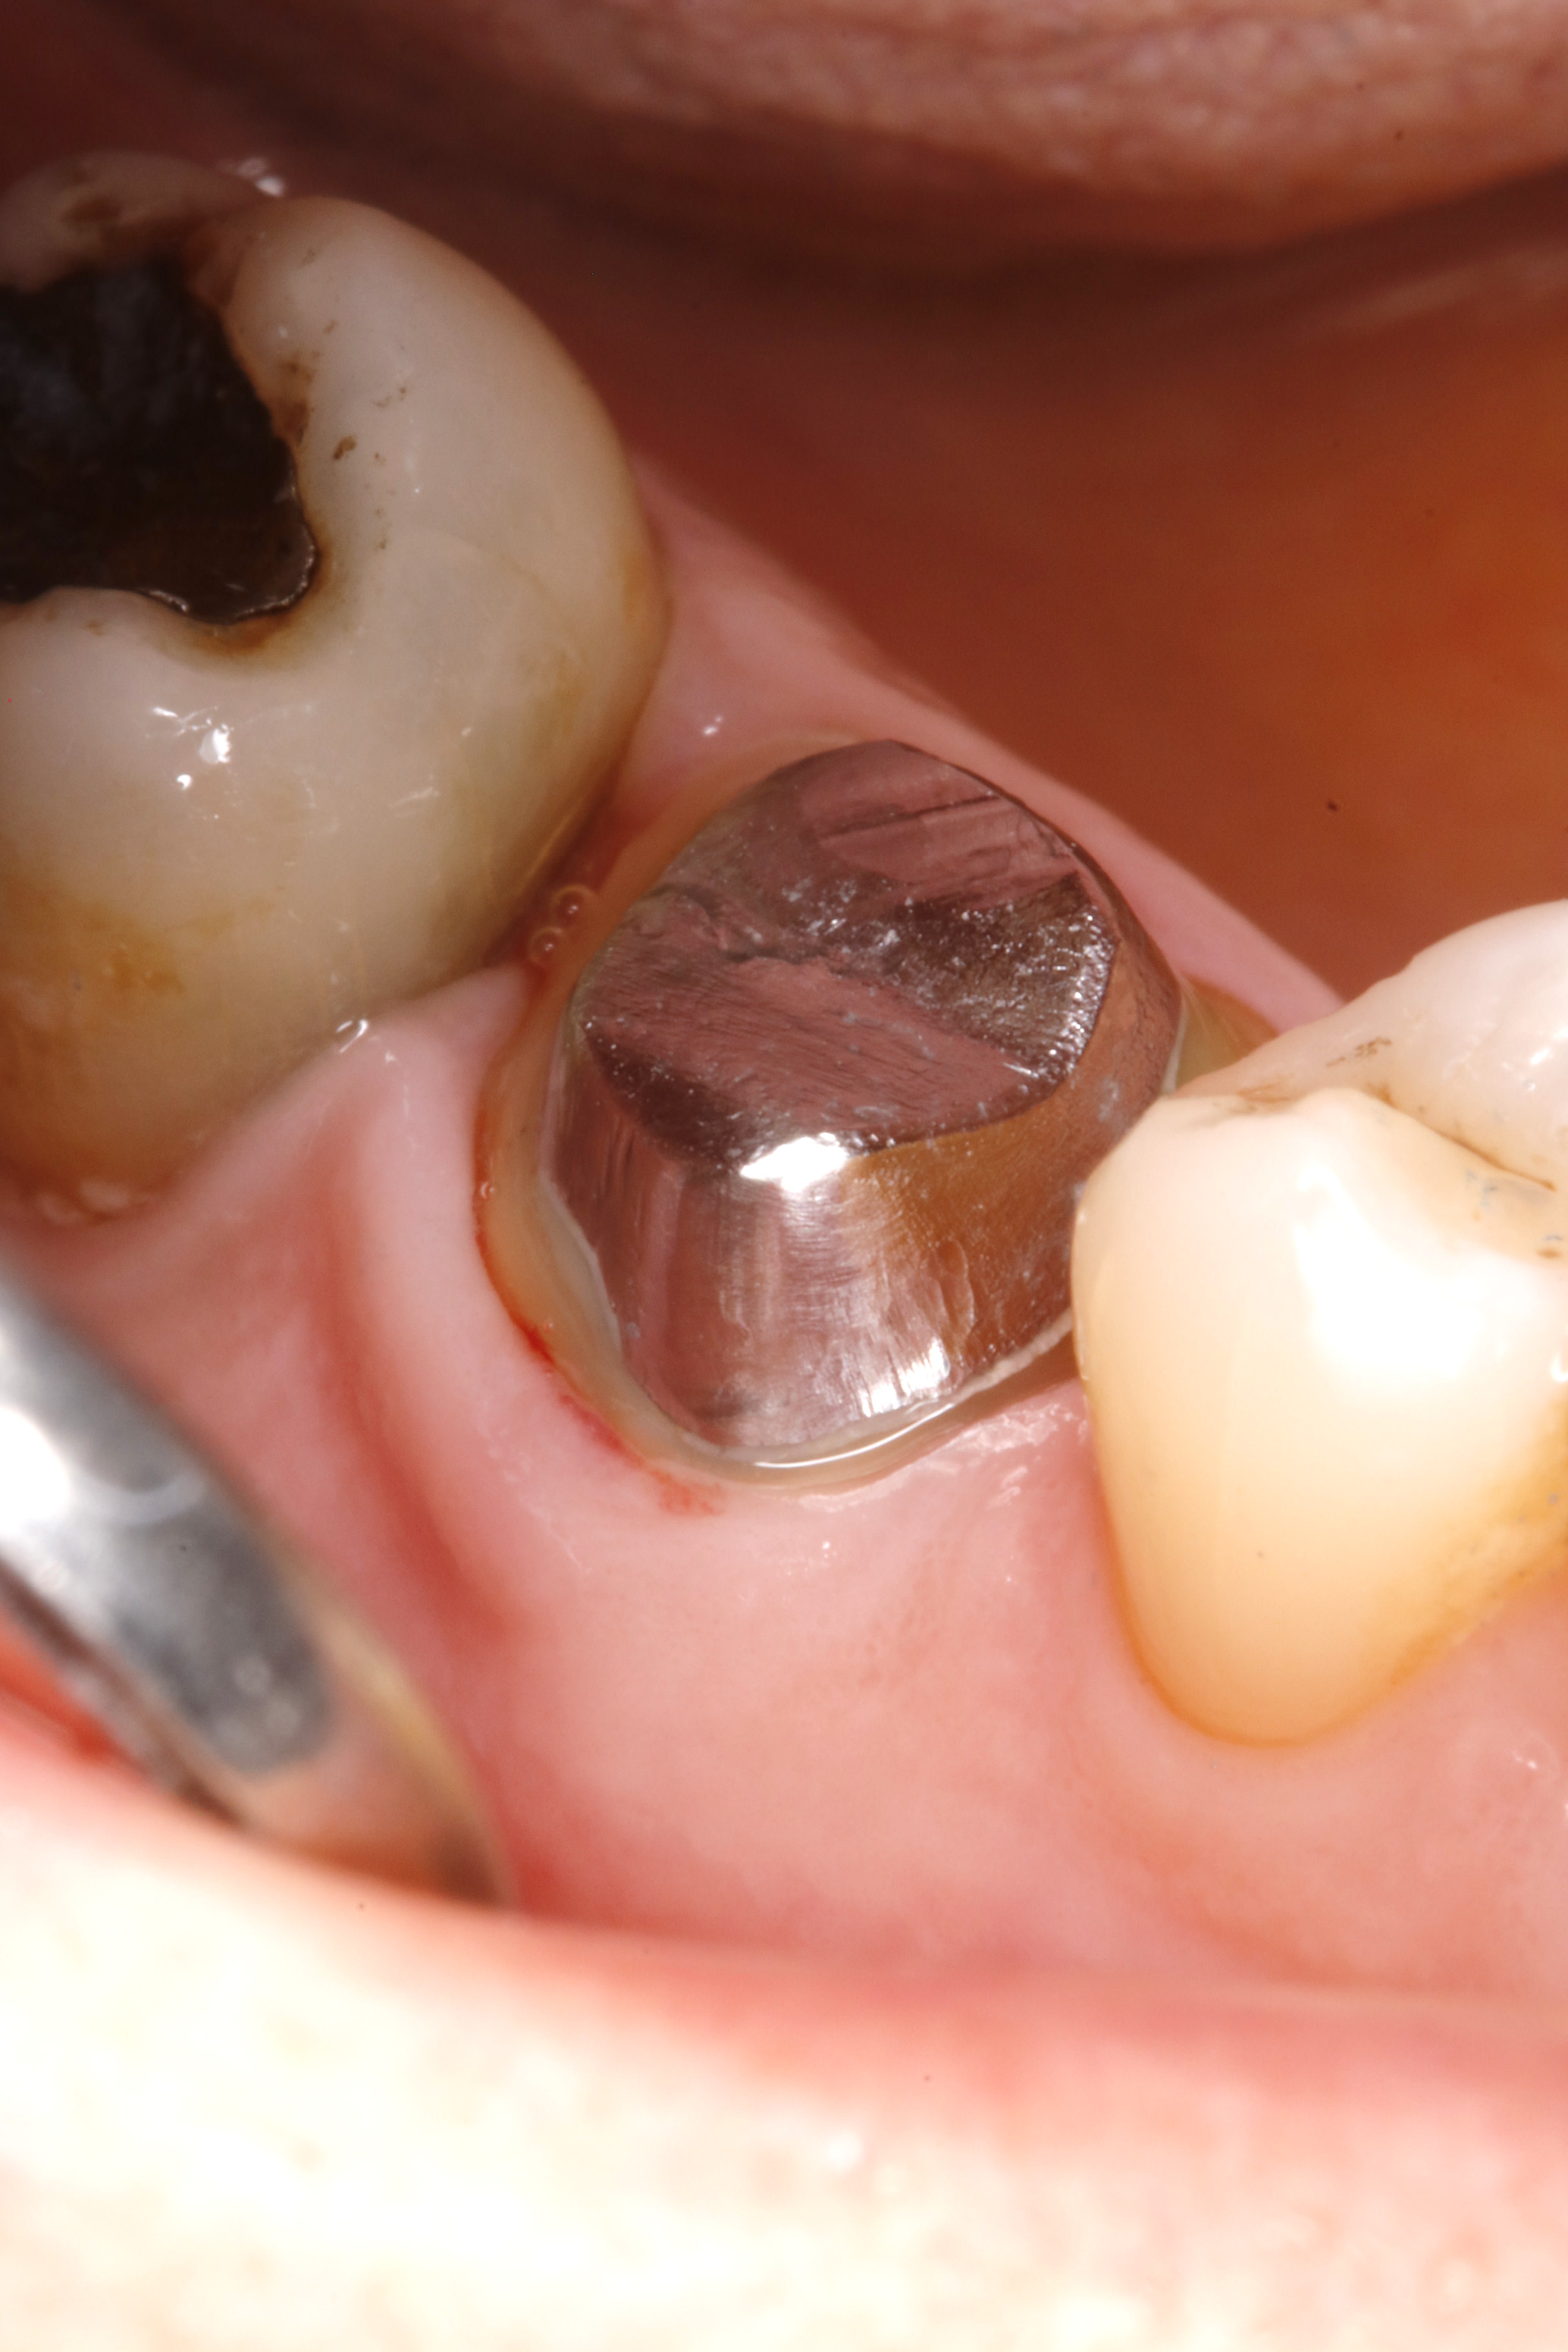

et là ç est le 1 er jour , le jour de l endo .

le but est de pretailler la dent en restant juxta .

en aucun cas ,il faut toucher la gencive le 1 ere séance . ( sauf s'il y a carie bien sur , mais ç est tres ponctuel ).